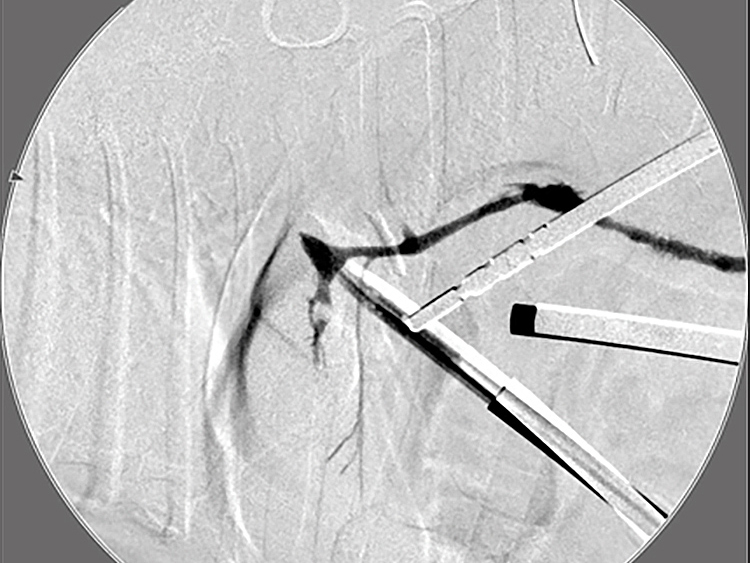

胆嚢の通路がちゃんと開通しているのか調べるために造影検査をしています。 この処置をすることで洗浄の効果と詰まりを確認することができます。

詰まりがないかを透視で確認しています。